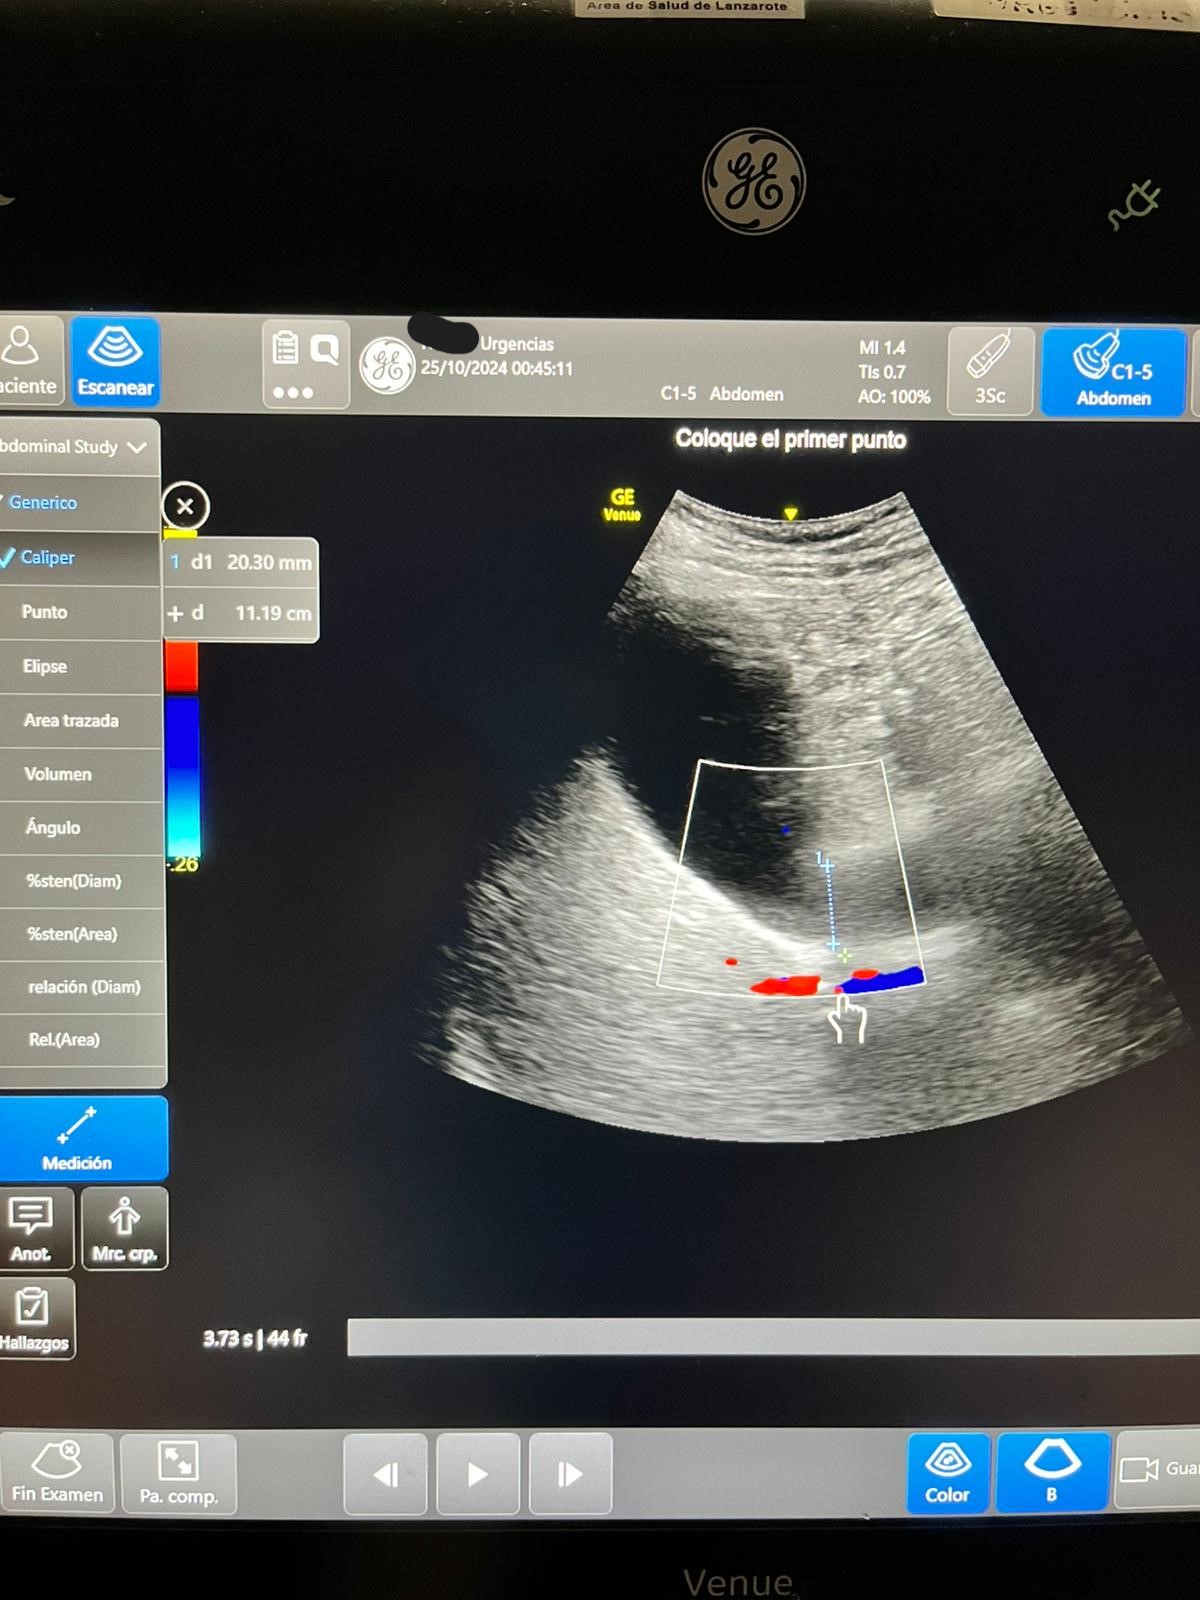

Ecografía: hígado y vías biliares normales sin formaciones expansivas. Coledoco de calibre normal.

Vesícula biliar distendida con litiasis múltiple suncentimétricas y barro biliar de paredes finas.

Páncreas y bazo sin alteraciones Riñones normales, sin dilatación de sistema excretor, urolitiasis ni lesiones expansivas sólidas. Quistes corticales simples en ambos riñones en tercio medio del izquierdo quiste complejo con tabiques finos y calcificación.